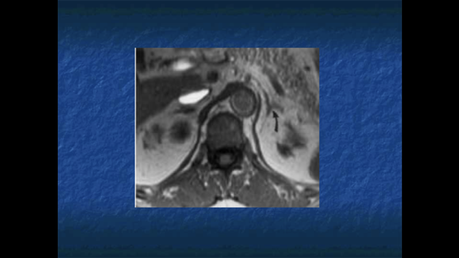

TOMOGRAFIA COMPUTARIZADA.

PERMITE IDENTIFICAR LAS GLANDULAS SUPRARRENALES EN MAS EL 95% DE LOS INDIVIDUOS, SI LOS CORTES SON DE POCO GROSOR

RESONANCIA MAGNETICA

PERMITE IDENTIFICAR LAS GLANDULAS SUPRARRENALES EN EN EL 100% DE LOS INDIVIDUOS.

PARA EL ESTUDIO DE LAS MASAS SUPRARRENALES, SE PUEDE RECURRIR Al ULTRASONIDO, LA TC, RM O A LA MEDICINA NUCLEAR.

LA TC ES CONSIDERADA COMO EL METODO DE ELECCION. SE RECOMIENDA UTILIZAR CORTES FINOS Y REALIZAR UN ESTUDIOS SIMPLE Y CONTRASTADO.